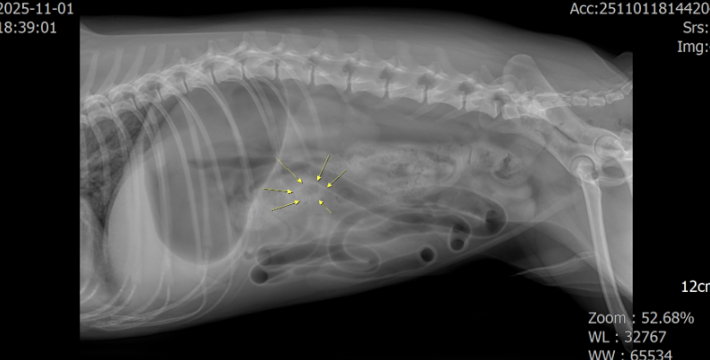

X-ray

소장의 이물 음영이 보이고 mechanical obstruction으로 인해 소장의 가스음영이 관찰되었고 더 명확히 이물의 존재 확인을 위해 초음파 검사가 진행되었습니다.

X-ray와 초음파 검사에서 소장 내 이물로 인한 장폐색 확인

X-ray상 여러 가스 찬 소장 고리가 겹겹이 보이면 obstruction을 의심합니다.